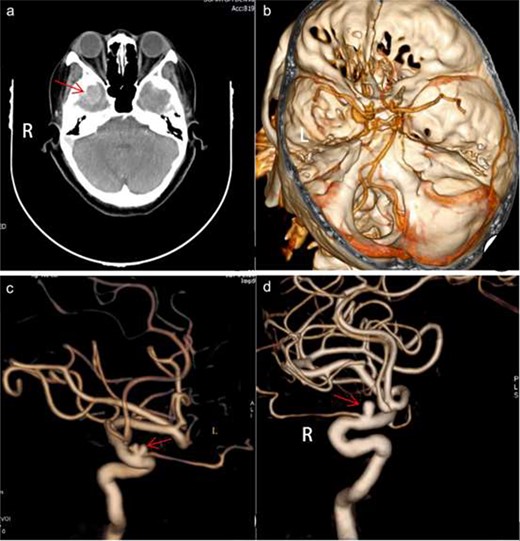

A 52-year-old female patient was admitted to the neurosurgery department of our hospital for a recurring headache, dizziness, and the appearance of a black shadow in the right eye experienced over 1 month. The patient had a history of hypertension, long-term use of amlodipine benzenesulfonate tablets, and self-reported blood pressure control. She was unable to tolerate magnetic resonance imaging (MRI). An enhanced computed tomography (CT) scan of her head revealed a clear circular shadow in the right temporal region of the brain. The shadow contained a diameter of ~ 1.9 cm and lesions were apparent with no obvious signs of edema. CT angiography (CTA) revealed small saclike projections in the supraocular segment of the bilateral internal carotid artery with diameters of ~ 0.3 cm. A digital subtraction angiography (DSA) revealed a cystic shadow with a size of ~ 3.2 × 3.8 mm and a cervical width of ~ 2.4 mm visible in the ophthalmic segment of the right internal carotid artery protruding upward and outside the vascular lumen. The left ophthalmic artery, showing a size of ~ 3.0 × 4.2 mm and a cervical width of ~ 2.6 mm, was seen at the beginning of the lobulated cyst-like process from outside of the lumen. The ophthalmic artery rose from below the neck of the aneurysm (Fig. 1a–d).

Preoperative imaging. axial CT demonstrated a clear circular shadow with a diameter of ~ 1.9 cm (a). A presurgical CTA revealed small cystic projections in the supra segment of the bilateral internal carotid artery bed process with a uniform diameter of 0.3 cm (b). Presurgical DSA revealed a cystic shadow that was visible in the ophthalmic segment of the right internal carotid artery protruding outside of the vascular lumen. The left ophthalmic artery was visible at the front of the lobulated cyst-like process arising from outside of the lumen. The ophthalmic artery rose from below the neck of the aneurysm (c and d). L, left; R, right.